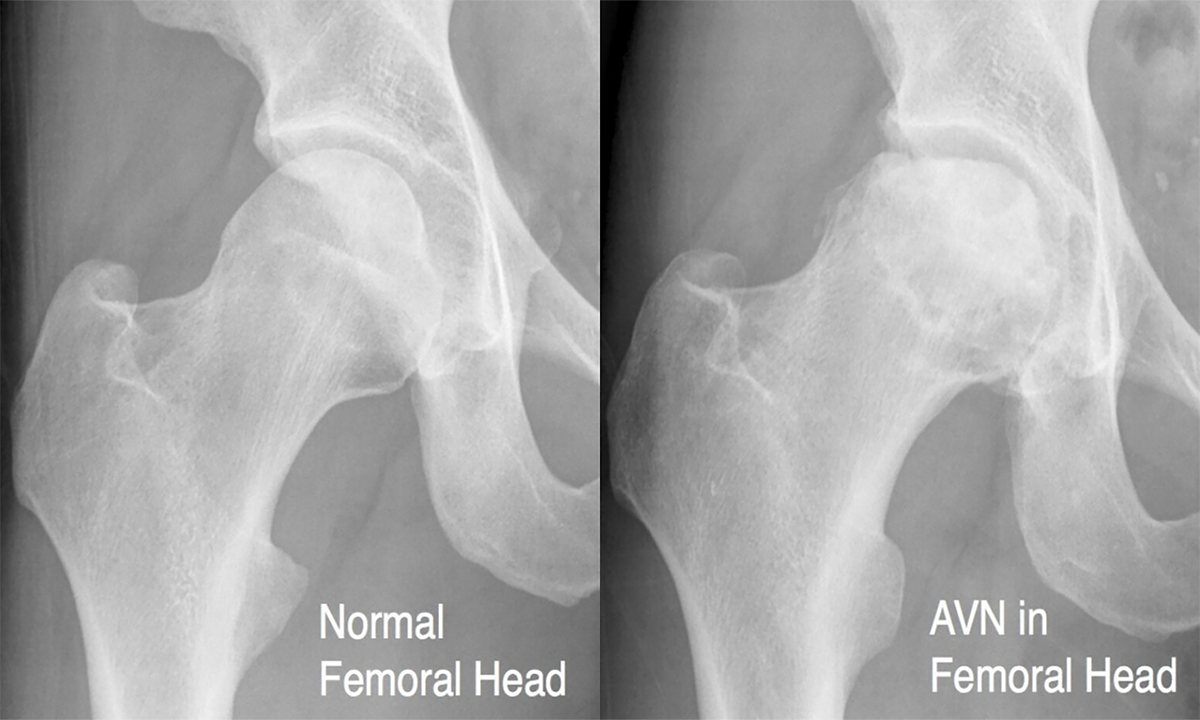

Avascular Necrosis (AVN), also known as Osteonecrosis, is a condition where the blood supply to the hip bone is reduced or completely cut off. Without enough blood, the bone tissue starts to die, leading to pain and joint damage. If left untreated, AVN can cause hip joint collapse, making movement difficult.

Early diagnosis is important to prevent joint damage. MRI, X-rays, and CT scans help detect AVN. Treatment options include: